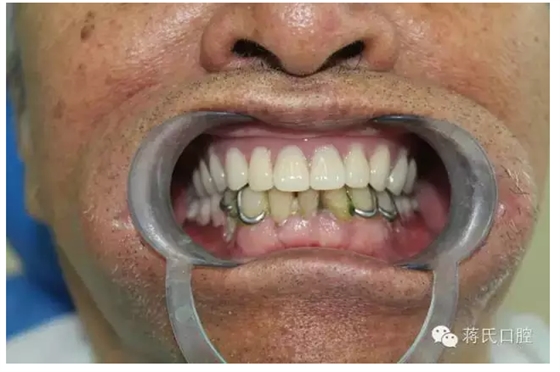

種植醫(yī)師 蔣志剛

主訴 要求修復(fù)缺失牙,因?yàn)樽陨懋愇锔兄兀延谕庠盒迯?fù)幾次義齒,均不能使用,要求花費(fèi)最少的錢解決吃飯問題。

患者情況 男 76歲 ,三類骨。腭咽反應(yīng)重。治療方案 1盡量減少種植費(fèi)用。

5去除上頜基托